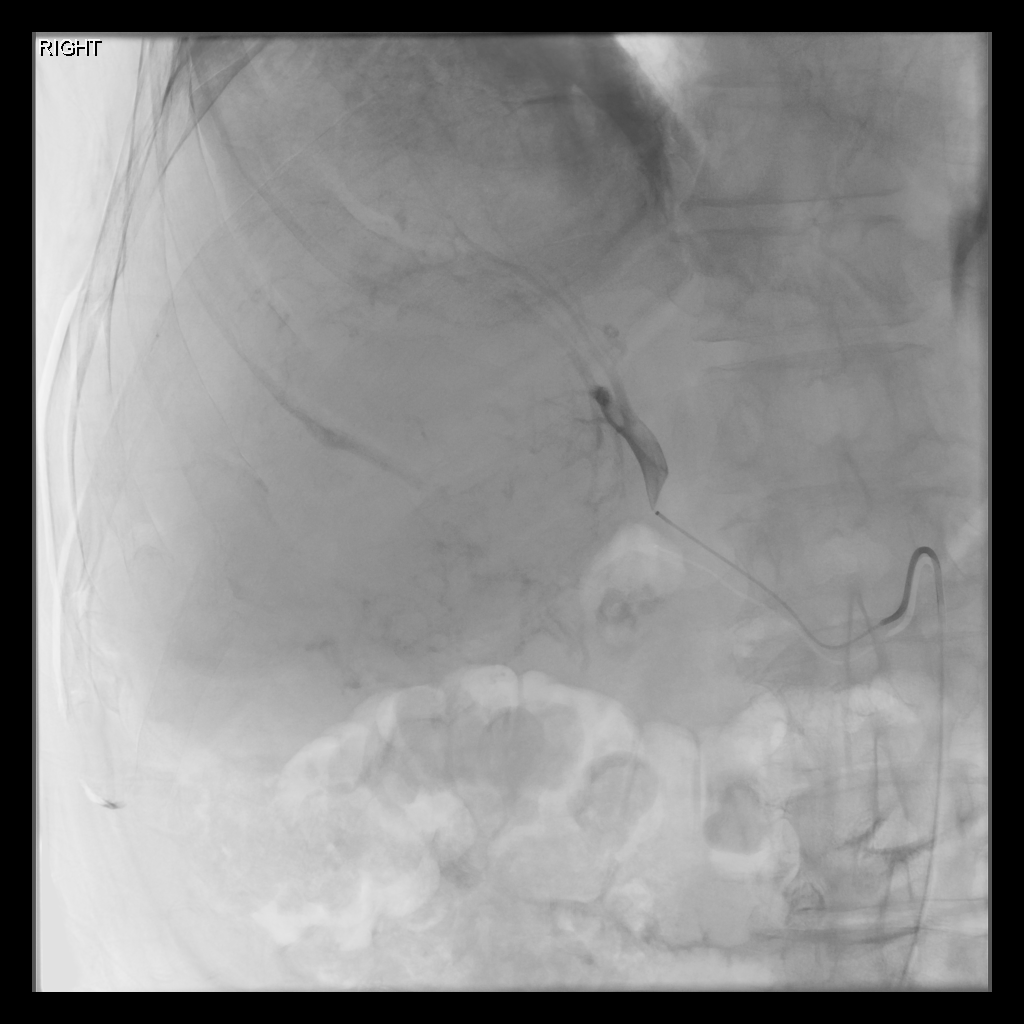

Mapping Angiogram

Comprehensive vascular mapping with CBCT to identify tumor supply and prevent extrahepatic deposition.

• Selective catherization

• Identify variant hepatic arterial anatomy

• Coil embolization of gastroduodenal or right gastric artery

• MAA injection to estimate lung shunt and dosimetry

Treatment Day

• Selective catheterization

• Deliver microspheres slowly under fluoroscopy

• Post-treatment SPECT or PET imaging